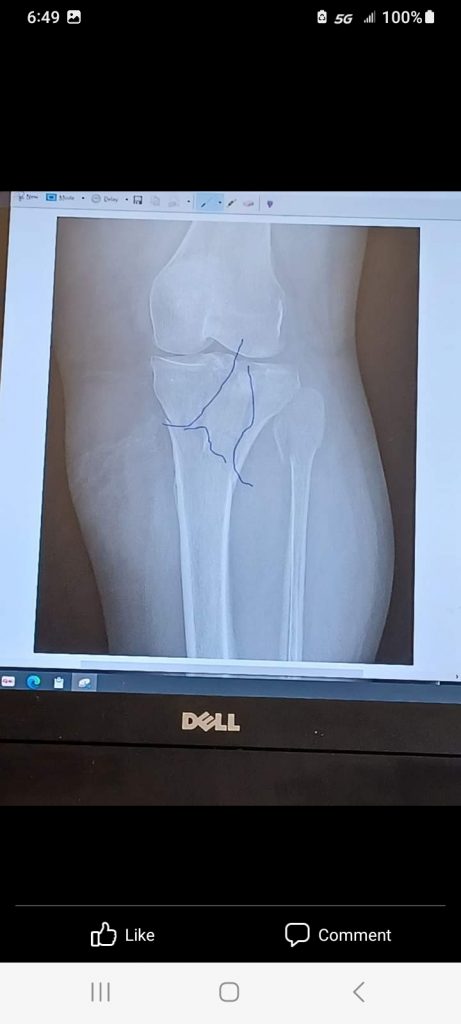

After 3 years recovered from my hip replacement surgery; Boom! Crack! Trauma! I fell and broke my knee and ankle. More specifically, a plateau fracture and a broken ankle. My tibia and fibula. Oh my goodness.

The ambulance came and transported me within an hour. I was checked in to my room and saw Dr. Aleksey Dvorzhinskiy that evening after I arrived. He had just finished another surgery and he was confident, kind, caring, smart and responsive to my needs. He reviewed my x-rays and scheduled my surgery.

Later that night, Dr. Dvorzhinskiy came to my room to visit with me and went over my new x-rays the next day. He showed me all the hardware that was inside my ankle and knee.